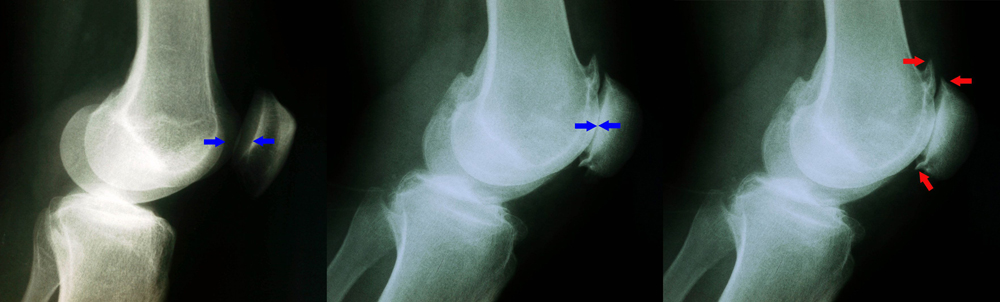

A Simple Radiographs Of A Patient Diagnosed With Patellofemoral Download Scientific Diagram